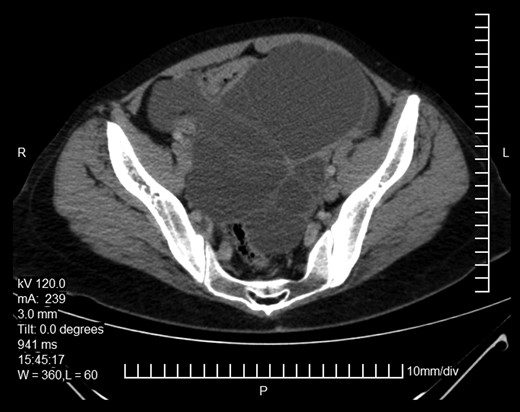

Here we report on a 32-year-old patient who presented at the Emergency Department complaining of acute abdominal pain accompanied by vomiting and diarrhea that had started three hours before. The patient was a para 2 and the latter delivery had occurred nine months before. She had been breastfeeding until 20 days before her ED visit and her menses had not yet resumed. Her medical history was unsignificant and she reported a laparoscopic ovarian cystectomy five years before, of which the histology report was not retrieved. She also had an ultrasound six months before, which described a pelvic multilocular cystic lesion of 11.4 × 8,6 × 12.3 centimeters, which remained untreated. The patient underwent an IV contrast—enhanced abdominal CT which demonstrated sizeable multilocular bilateral ovarian cystic lesions, of 18 cm and 15 cm in dimensions (in the right and left ovary respectively). (Figs 1 and 2). Her tumor markers were as follows (normal values are in parentheses): CA 15.3 = 20.53 U/ml (<25 U/ml), AFP = 1.08 ng/ml (<7 ng/ml), CEA = 0.63 ng/ml (<3.8 ng/ml), CA 125 = 110.40 U/ml (<35 U/ml), CA 19.9 = 50.06 (<34 U/ml), CA 72.4 = 6.74 (<6.9 U/ml). After the completion of preoperative investigations, the patient underwent and exploratory laparotomy. Frozen section revealed bilateral serous borderline tumors, therefore the patient underwent a total abdominal hysterectomy/bilateral salpingoophorectomy and epiplectomy. During surgical procedure astonishing remarks was the necrotized torsion of ovarian masses mimicking infiltrated ovarian neoplasm. (Figs 3–5). The final histology report confirmed the diagnosis of bilateral serous borderline tumors/atypical serous proliferative tumors, staged as pT1cNxMx or FIGO Ic. (Figs 6 and 7). Peritoneal fluid cytology showed mesothelial reactive lesions. The patient’s postoperative course was uneventful. The Multidisciplinary Team Meeting decided on adjuvant chemotherapy (four cycles of CarboTaxol; paclitaxel and carboplatin). Nine months after surgery, the patient remains alive and disease – free.

Abdominopelvic CT. Bilateral ovarian masses with characteristic diaphragms.